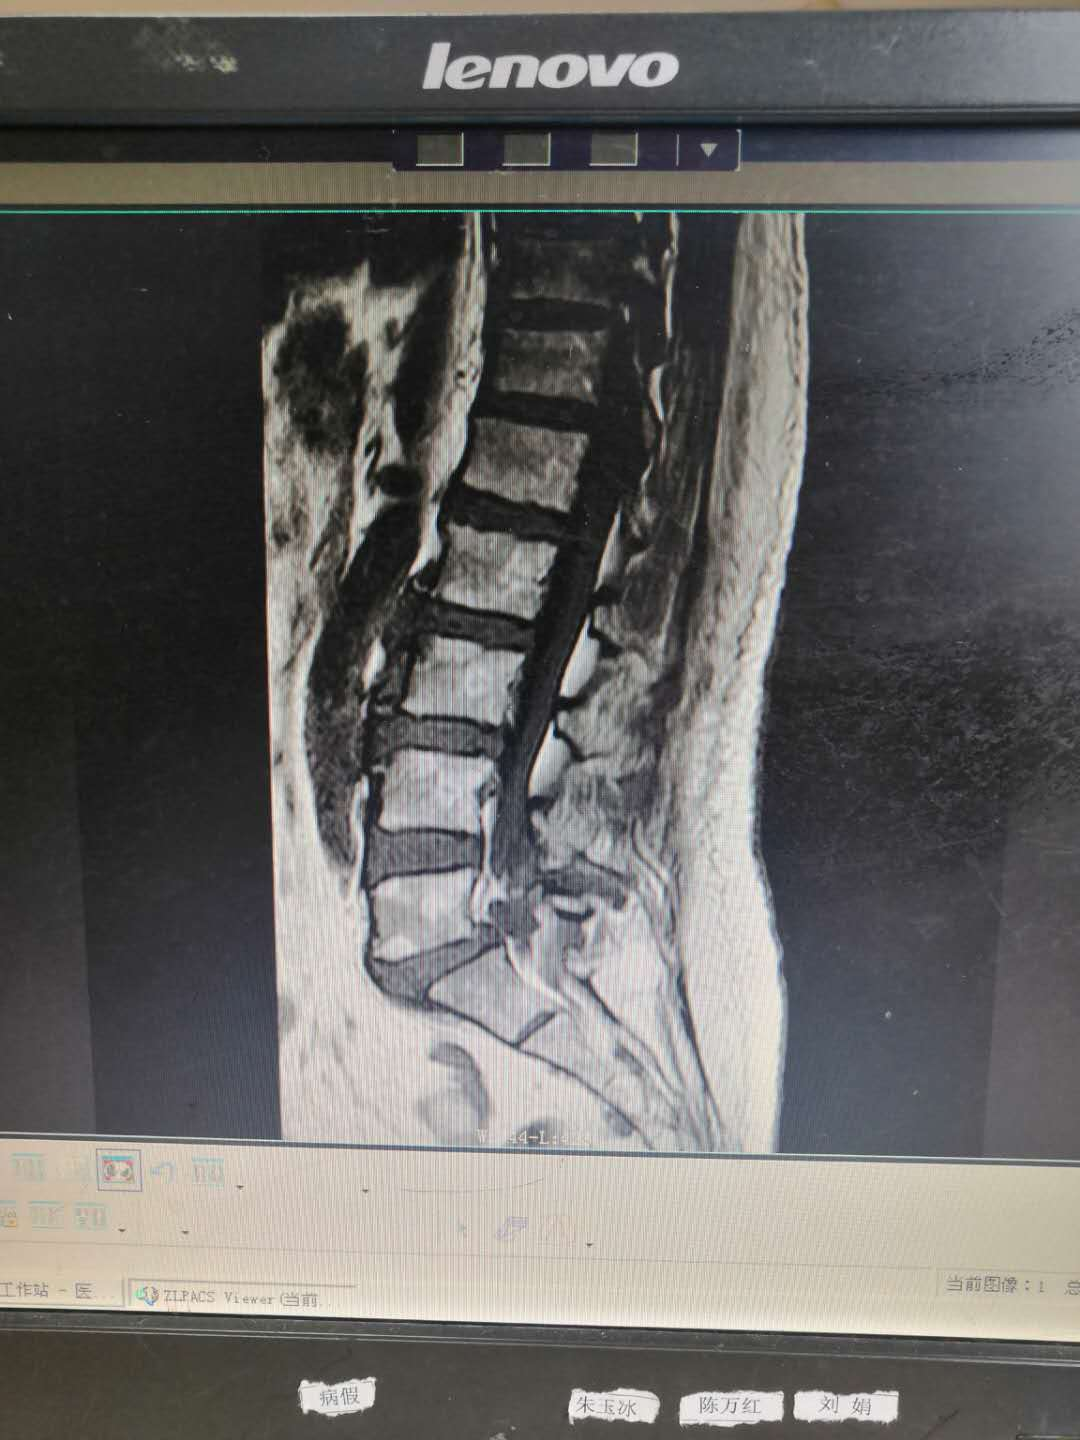

主   诉:因反复腰痛伴右下肢疼痛麻木8年,加重6月,入院治疗。

现病史:缘于8年前开始无明显诱因出现腰部疼痛,呈间歇性胀痛,持续时间数分钟至数小时不等,放射至右下肢,伴右下肢麻木,此后症状反复出现,持续时间数小时至数天不等,劳累后加重,休息后缓解,6月前加重,并出现间歇性跛行,目前行走约200米左右需休息后方能继续行走,在当地医院治疗(药物+理疗)后效果欠佳,现特至我院就诊。

专科检查:颈胸椎各棘突无明显压痛,颈部活动正常,L3-5棘突及椎旁存轻压痛及叩击痛,疼痛无放射,腰部屈伸活动轻度受限,右下肢直腿抬高试验阳性(40度),加强试验阳性,双侧跟臀试验阴性,拾物实验阴性,右侧股四头肌、右足拇背伸肌力约4级,右小腿后、外侧、足背、足底感觉较左侧减退,肢端血运正常。

术前影像资料:

诊       断:

腰椎滑脱症(腰5向前III度)并腰椎管狭窄症。